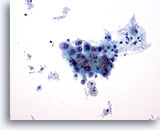

画像 2

肺FNA、肺大細胞癌明瞭な細胞縁を呈するシート状低分化癌細胞。細胞は統制されておらず、局所的に核の重積が見られます。背景には何も見られず、腫瘍性背景を呈していません。腫瘍細胞には、扁平上皮ないし腺管への分化に特異的な特徴は認められません。

40倍

画像 2

肺FNA、肺大細胞癌

明瞭な細胞縁を呈するシート状低分化癌細胞。細胞は統制されておらず、局所的に核の重積が見られます。背景には何も見られず、腫瘍性背景を呈していません。腫瘍細胞には、扁平上皮ないし腺管への分化に特異的な特徴は認められません。

40倍